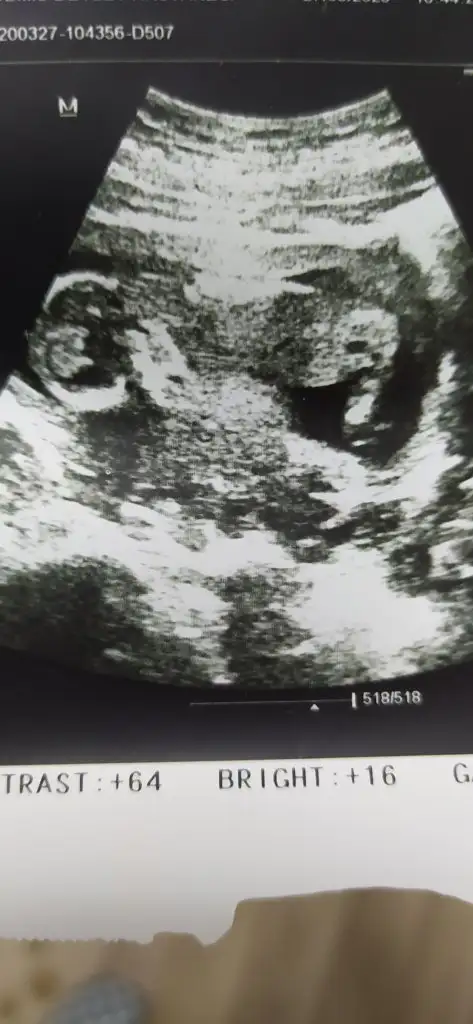

Mrb 13 haftalık cinsiyetine bakarmısınız

Net olmayanlarıda tekrar cektim bidaha onlar 13 hafta diğerleri 11 hftalık